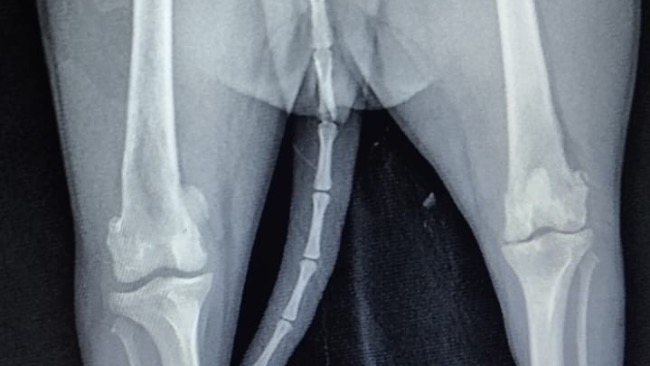

Kochani, pod naszą opiekę trafiła młodziutka szpicka. Niestety podczas konsultacji ortopedycznej okazało się, że jej łapka jest do natychmiastowej operacji. Zamiast radosnego życia młodziutkiego psa, żyje z permanentnym bólem, który uniemożliwia jej normalne poruszanie się. Bella praktycznie cały czas porusza się na trzech łapkach. Koszt operacji 3500-4000zl. Nie mamy wyjścia, musimy zrobić operację. Sunia cierpi, praktycznie nie używa łapki, z powodu ogromnego bólu. Niestety termin operacji jest uzależniony od tego, jak szybko uda nam się zebrać potrzebną kwotę… Liczy się czas i dosłownie każda wpłacona złotówka. Bardzo prosimy was o wsparcie Belli ❤️